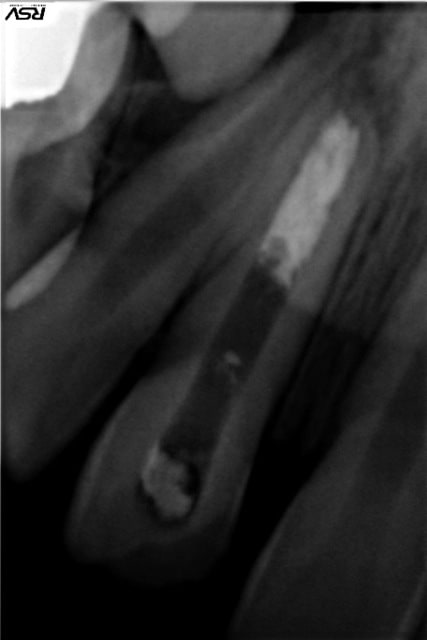

Patient, 20 ans, choc multiples sur les centrales étant gamin. Pano pour les 8.

Lésion sur 21, en bouche, légère dyschromie, test froid négatif, pas de douleur, retro, tu m'étonnes ... ! Les autres répondent correctement.

Concrètement, comment obturer convenablement ça ?

Bouchon de MTA : entre la galère pour appliquer ça correctement à l'apex et sans dépasser dans tous les sens, bof, de plus j'imagine que c'est utopique de vouloir obtenir ne serait-ce qu'un début de fermeture apicale.

Cônes de gutta moulés avec moultes Rx..., pourquoi pas, déjà fait, mais l'étanchéité ne semblerait pas optimale, ajouté au fait que le peu de ciment risque de fuser également.